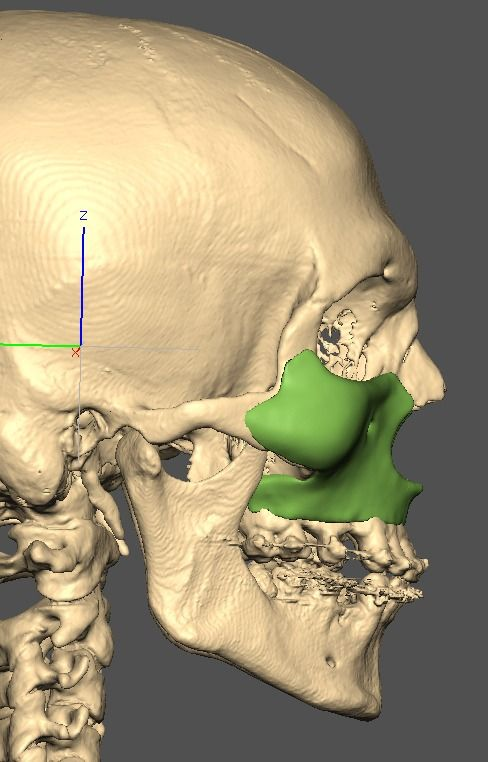

I know a guy who designed this for himself in collaboration with an asian implant company.

Not the final product yet, he is making adjustments as we speak.

Giant and Eppley were the inspiration